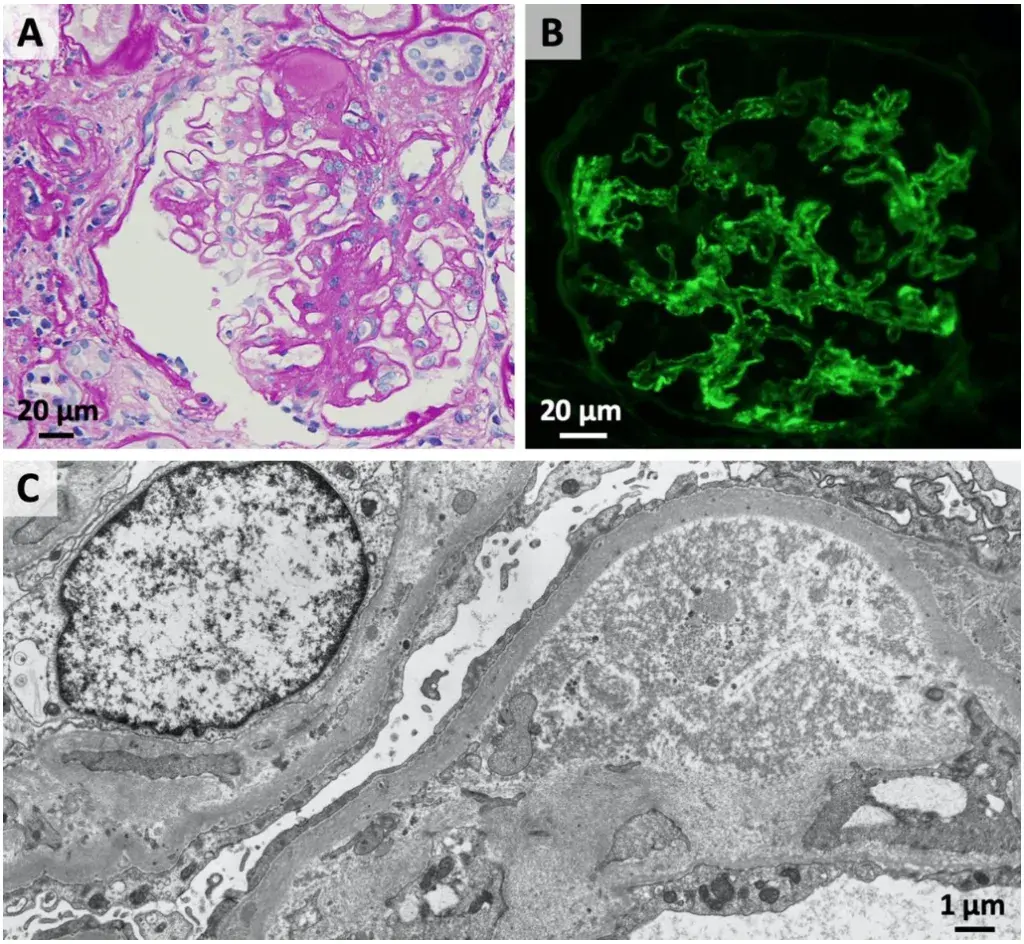

A microscopia de luz revelou glomérulos com lesões insudativas, hialinização arteriolar e proliferação mesangial (Figura 1A), mas **nenhuma** lesão ativa da nefrite lúpica foi identificada. A imunofluorescência mostrou **apenas** deposição linear de IgG ao longo da membrana basal glomerular com escassa deposição granular (Figura 1B). A microscopia eletrônica demonstrou apagamento do processo podocitário e espessamento da membrana basal.

Esses achados foram diagnósticos de **nefropatia diabética sobreposta a lesões crônicas de nefrite lúpica**.